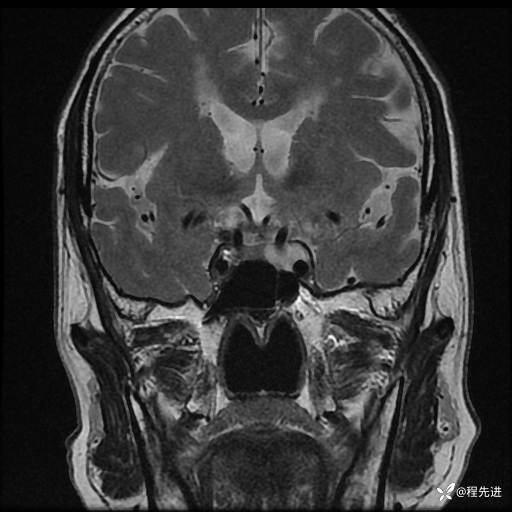

MRI平扫+增强:

T2: